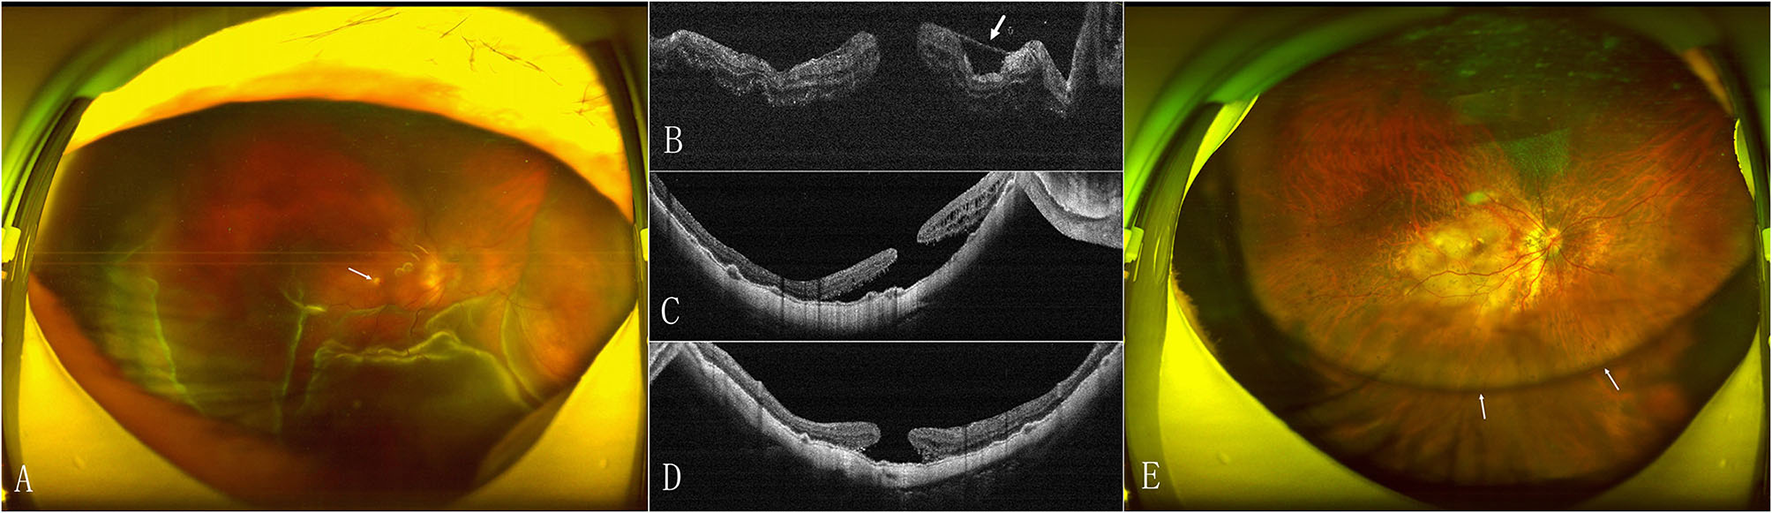

The MH closed after the initial surgery in 15 (53.6%) eyes in the face-down group and 18 (72%) eyes in the adjustable group (Figure 1). The retinal reattached after initial surgery in 28 (100%) eyes in the face-down group (Figure 2) and 24 (96%) eyes in the adjustable group. There was no significant difference in the rate of MH closure (p = 0.167) and retinal reattachment (p = 0.472) between the two groups. Only one patient in the adjustable group did not achieve an MH closure and retinal reattachment. During the follow-up, she was unwilling to undergo another surgery, but the extent of retinal detachment gradually narrowed, and the MH was still not closed until 21 months after surgery (Figure 3). There were 15 eyes (53.6%) and 11 eyes (44%) with high IOP after surgery in the two groups (p = 0.487). All eyes with high IOP were controlled within the normal range after the treatment with anti-glaucoma drugs, and no surgical intervention was performed. There were no retinal detachment and other complications occurred during the follow-up.

Figure 1

Preoperative and postoperative scanning laser opthalmoscope (SLO) and optical coherence tomography (OCT) images of the eye of a 56-year-old woman with macular hole retinal detachment (MHRD) in the adjustable positioning group. (A) SLO shows the retinal detachment (RD) beyond vascular arcade (arrow). (B) Preoperative OCT confirms the macular hole (MH). (C) OCT shows MH closure and retinal reattachment with inserted internal limiting membrane (ILM) tissue (arrow) plugged into the hole at 2 weeks after surgery. (D) OCT shows the foveal microstructure recovery in eyes with MH closure at 6 months. (E) SLO shows silicone oil emulsification (white arrow) and chorioretinal atrophic lesion (black arrow) at 6 months.